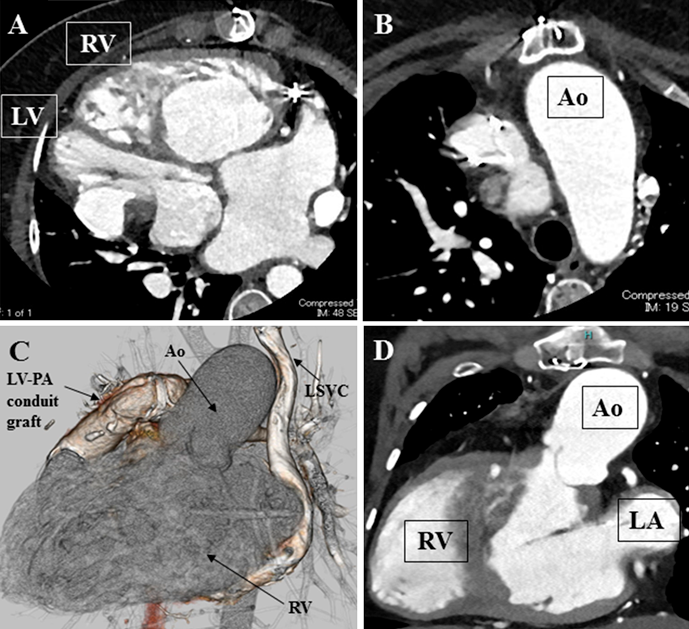

造影CT検査(Fig. 2)

Fig. 2 Preoperative computed tomography

(A and B) Right ventricle and aorta are just behind the sternum. The ascending aorta with the diameter of 40 mm. (C)The frontal view of the three-dimensional contrasted computed tomography. (D) The coronal section. Ao, aorta; LA, left atrium; LV, left ventricle; RV, right ventricle.

大動脈が胸骨に近接している.左上大静脈遺残をみとめ,右心房に流入している.上行大動脈拡大あり(最大径:40 mm).ペースメーカーリードは,右鎖骨下静脈より上大静脈を経由して右心耳,左心室心尖部にそれぞれ留置されている.